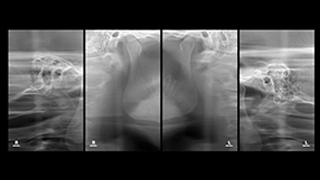

SMILE FACE DENTAL CLINIC’s 12-step orthodontic diagnostic system is an advanced process that systematically analyzes a patient’s teeth, jaw structure, facial balance, and bite, allowing us to establish the most optimal treatment plan.

04 Jaw Joint Examination

05 Frontal X-ray